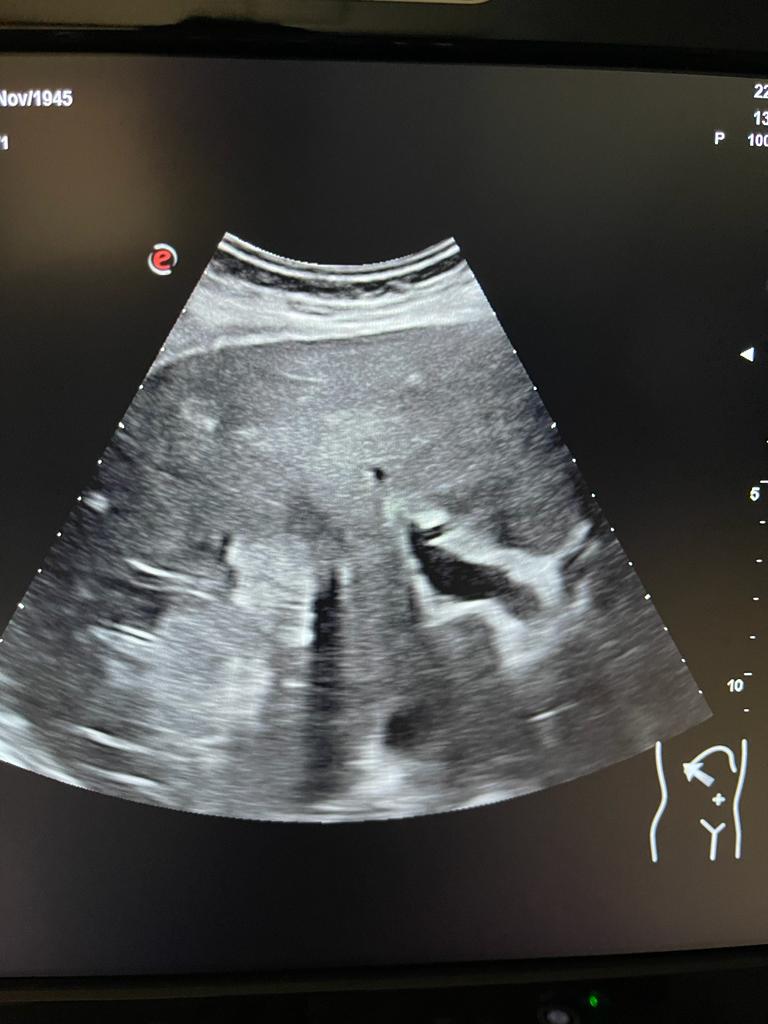

Se aprecia hígado heterogéneo con múltiples LOES hepáticas hiperecogénicas (una de ellas de unos 7x7 cm), sin captación de doppler. Al menos otras 2 LOES de menor tamaño presentan halo hipoecoico. Vesícula replecionada de contornos lisos y sin litiasis en su interior. Ambos riñones visualizados de tamaño normal y sin datos de hidronefrosis.